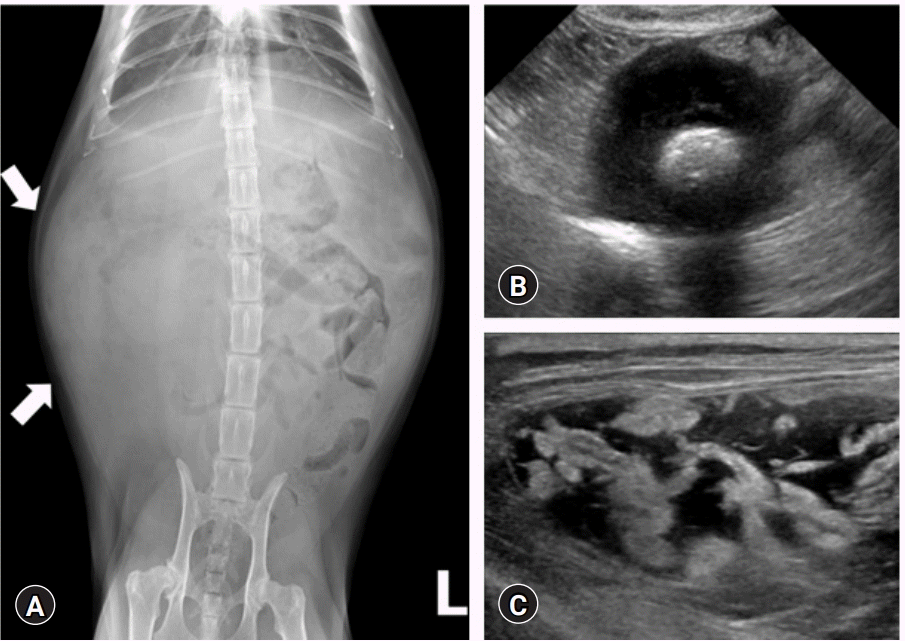

Ультразвуковое исследование: Ультразвуковое исследование является важным инструментом для диагностики асцита у кошек. Оно позволяет ветеринарному врачу визуализировать брюшную полость и определить наличие скопления жидкости. Ультразвуковое исследование также может помочь выявить возможные причины асцита, такие как опухоли, воспаление или инфекция.

Диагноз асцита у кошек обычно устанавливается с помощью физического обследования, пальпации живота, а также дополнительных диагностических методов, таких как ультразвуковое исследование брюшной полости, анализы крови и мочи, рентгенография и биопсия.

Для диагностики асцита важно обратить внимание на клинические признаки. У кошек с асцитом можно заметить увеличение размеров брюшной полости, что придает ей выпуклую форму. Кошка может также проявлять симптомы дискомфорта, слабости, потери аппетита и повышенной заметности дыхания. Для подтверждения диагноза может потребоваться анализ абдоминальной жидкости, который поможет определить ее состав и потенциальные причины.

Инструментальные исследования: Для более точного выявления причин асцита могут потребоваться дополнительные инструментальные исследования, такие как ультразвуковое исследование брюшной полости, рентгенография, компьютерная томография (КТ) или магнитно-резонансная томография (МРТ). Эти методы позволяют врачу получить более детальную информацию о состоянии внутренних органов и выявить возможные изменения.